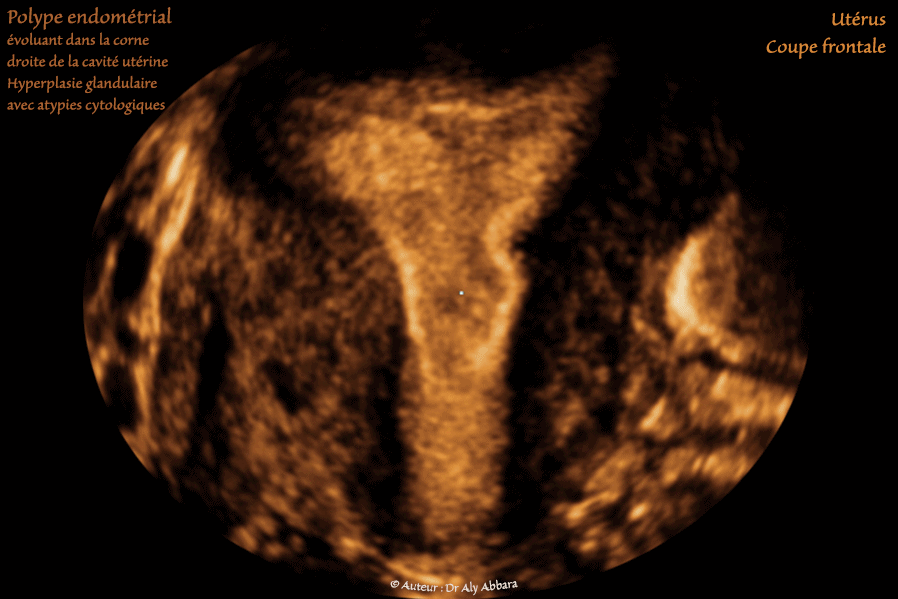

Utérus : Polype endométrial de structure hyperplasique glandulaire simple et complexe avec un foyer d'atypies cytologiques nucléaires :

• Images échographiques montrant (sur une coupe frontale, puis des coupes para-sagittale droite et transverse) la présence au fond utérin, dans la corne droite, la présence d'une formation polypoïde mesurant 14 x 9 x 8,4 mm (soit 0,6 cm3).

L'endomètre lors de la réalisation de cette échographie était en phase proliférative (11° jour du cycle menstruel).

La ligne de vacuité utérine présente une solution de continuité au niveau du site de l'insertion du polype endométrial qui paraît comme une formation ovoïde plus échogène que l'endomètre juxtaposé.